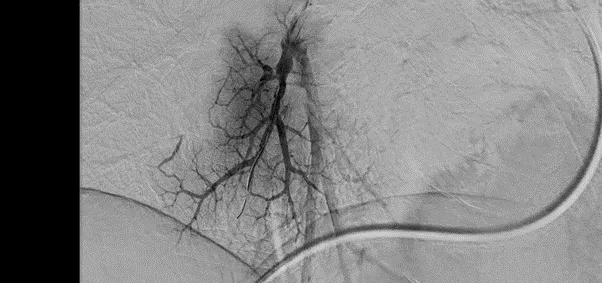

Позволяет получить идеально четкую картинку сосудов без помех от костей. Процесс происходит автоматически за доли секунды. Аппарат делает снимок до введения контраста, затем серию снимков с контрастом. Первое изображение компьютер накладывает на снимки с контрастом и убирает все, что совпало. Кости черепа, ребра или позвоночник полностью исчезают с экрана. Хирург видит только четкое дерево кровеносных сосудов на пустом фоне. Это позволяет заметить мельчайшие тромбы, аневризмы или сужения размером менее миллиметра.

- Ангиография нижних конечностей

Картирование кровотока в ногах при диабете или атеросклерозе для планирования операции по восстановлению проходимости.